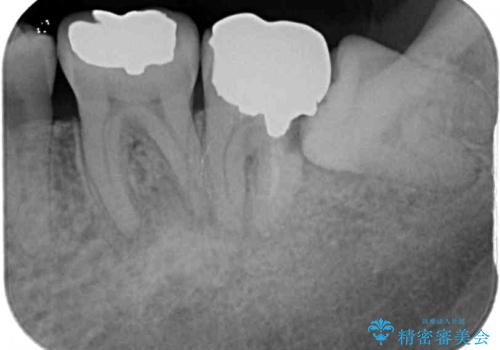

また、左下の奥歯は親知らずの影響で手前の歯の歯根までむし歯になってしまったため、親知らずとともに抜歯をし、インプラントによる補綴治療を行うこととしました。

インプラント埋入による仮歯の装着や、前歯の反対咬合の改善は比較的スムーズに達成されましたが、舌突出癖などの影響による、歯列全体のスペースを閉じることが難航し、期間がかかってしまいました。